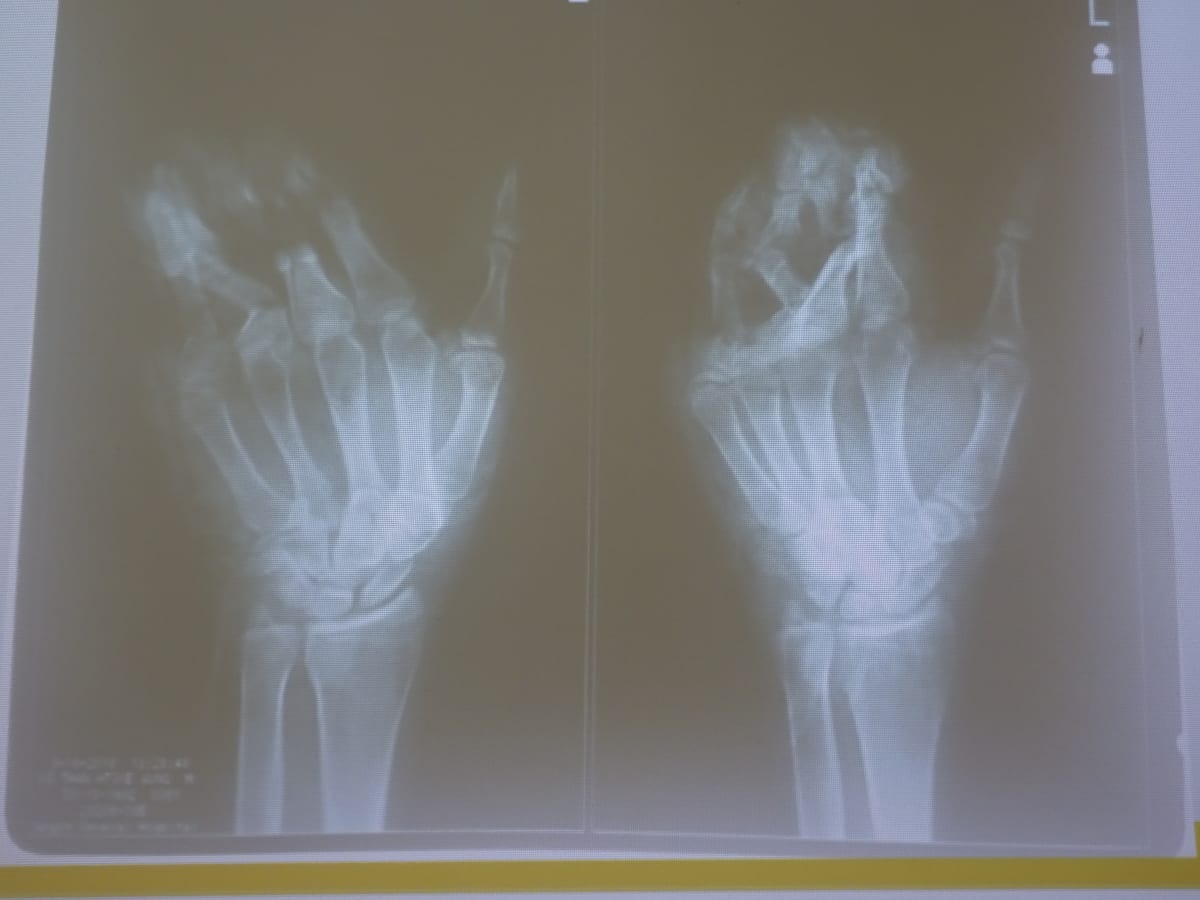

As a senior consultant (in hand and general orthopedics), I provided feedback during the morning fracture conference (“audit”), where the on-call resident presents admissions from the previous 24 hours. The majority of these patients are polytrauma victims from road traffic accidents. Trauma affects the poor disproportionately. Traffic is chaotic and poorly regulated. Industrial injuries are also common. In my first week I saw three patients with injuries from sugar cane juicing machines alone. The safety guards on the juicing machines had been removed. These hands were mangled, with extensive bony and soft tissue damage, with little hope for regaining much function.

The Hand Surgery Unit is skilled in microsurgical procedures, including fistula placement and brachial plexus surgeries. I observed a para-umbilical, antero-lateral thigh, groin, and supra-malleolar flaps. I rarely do flaps in my community-based practice in the US, so I was of limited help in these cases. I was more useful in bony and ligamentous surgeries, such as multiple metacarpal fractures, a scaphoid dislocation, and a base of the thumb metacarpal fracture.

When not in the operating theatre, I staffed the outpatient clinics. Many poor patients don’t seek care until the injury becomes disabling, resulting in chronic dislocations and malunions. We saw an incarcerated 34-year-old man who had a neglected mid-shaft both bone fracture which had gone on to malunion. He presented with a deformed and painful forearm. We rounded on him in the hospital jail, located in the dungeon of the building. His surgery involved shortening and plating the fractures.

As is often the case, I learned as much as I taught. I saw examples of tuberculosis in the upper extremity, including the elbow and wrist. The wrist masses clinically appeared to be ganglions but were in fact “melon seed” granulomas of the wrist and hand. Occasionally there were heartbreaking cases with no easy solutions. There was a case of a 53-year-old man who had been diagnosed with a sarcoma of his forearm the prior year. He had been lost to follow-up, and now presented with a massively enlarged right arm, lymphedema, and nerve compression. Given the aggressive extent of the tumor, he was likely to lose his arm (if not his life).